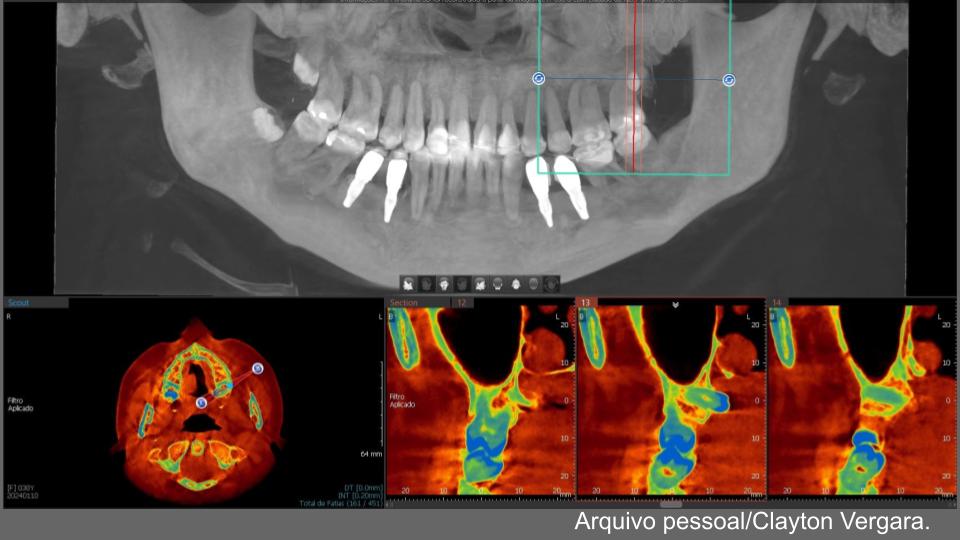

Virtobot atualizou o anterior. Atualmente com sua nova versão atualizada, o Virtobot melhorou a precisão da biópsia e está focado em agilizar o fluxo de trabalho e aumentar o nível de automação. Recentemente, técnicas mais avançadas de digitalização 3D foram introduzidas, permitindo imagens multiespectrais de corpo inteiro. A imagem utilizou fotogrametria multiespectral de 365 nm a 960 nm usando uma câmera digital com melhorias nas fontes de luz ultravioleta e infravermelha próxima e filtros de lente para revelar possíveis traços dentro do corpo. Fluidos corporais, hematomas, etc. Para detectar cadáveres através da arcada dentária (Crânio Facial), é utilizada outra ferramenta de radiologia forense a virtual autópsia dentária, a mesma foi projetada para melhor atender às necessidades dos setores judicial e criminal.

O Instituto de Identificação Humana da Universidade de Turim e o Gabinete de Assuntos Médicos e Jurídicos lançaram um projeto de pesquisa em 2020 com base na hipótese de que o processo de identificação de corpos não identificados deve sempre seguir os melhores protocolos para esclarecer a identificação de corpos, disse,( Nuzzolese, E. 2021). deve sempre incluir um exame odontológico completo para complementar e documentar a autópsia mesmo quando um dentista forense não estiver no local. Além disso, ferramentas virtuais em medicina e odontologia também podem ser utilizadas em medicina forense, especialmente para identificação pessoal,após a pandemia de COVID-19 e o risco potencial de infecção obrigou as instituições forenses a realizar autópsias virtuais sem comprometer as informações técnicas fornecidas pelo dentista forense. Atualmente, poucos departamentos ao redor do mundo reconhecem a viabilidade da autópsia tele dental, mas algumas instituições oferecem consultas remotas em odontologia legal para identificação pessoal ou oferecem este serviço por motivos humanitários. O projeto reúne temas de pesquisa como patologia, odontologia, antropologia e arqueologia, sob a égide dos direitos humanos dos mortos e da odontologia forense humanitária. O termo VIRDENTOPSY é uma combinação dos termos “virtual” e “anatomia dentária”. Esta é uma marca registrada de um site dedicado a fornecer avaliação odontológica forense remota de dados dentários post-mortem de restos mortais não identificados. O uso de radiografias em odontologia legal visa facilitar a identificação de corpos por meio do exame de detalhes anatômicos que podem ser utilizados como parâmetros. Isso inclui o formato dos dentes e raízes, dentes ausentes e existentes, raízes remanescentes, dentes supranumerários, fricção e desgaste e fraturas radiculares, grau de

reabsorção óssea devido à periodontite, lesões ósseas, diastema, formato e linha da cavidade, cáries, terapia endodôntica, pinos intrarradiculares e próteses dentárias. (Eastman, R., Raibley, et al 1982).

O processo de identificação de restos mortais não identificados deve respeitar os mais elevados padrões forenses e deve incluir sempre a recolha de todos os dados de identificação post-mortem. A tomografia cone beam(TCFC) é um método radiológico caracterizado por alta resolução espacial e baixa dose de radiação, adequados para diagnóstico prognóstico quando são identificados resíduos desconhecidos. Esses métodos permitem obter imagens precisas e detalhadas das estrutura dentárias e craniofaciais, essenciais para a identificação post mortem de indivíduos.Este processo requer a comparação de pessoas desaparecidas correspondentes com dados ante-mortem documentadas e a reconciliaçãofinal de todos protocolos(Da Luz Silva, W., Dias, R. S., Vergara, C. S., & De Sá, L.

- 2023). Neste contexto, uma autópsia dentária completa e uma avaliação adicional de todos os achados dentários por um dentista legista são essenciais para obter um perfil biológico geral e um exame geral.Simples exames dentários e recolha de dados dentários sem avaliação por especialistas em odontologia forense e identificação de vítimas não podem dar um contributo tangível para uma identificação pessoal atempada e eficaz. É necessária uma recolha e análise mais abrangentes de dados post-mortem quando se consideram os fenómenos migratórios Em Itália, o Projecto Migrantes Desaparecidos estima que houve 124 mortes e desaparecimentos de migrantes desde 2014, e mais de 60 dessas vítimas não foram identificadas As avaliações odontológicas forenses, por outro lado, limitam-se a exames odontológicos de não vítimas.Dentistas forenses experientes parecem estar rotineiramente envolvidos as aplicações de anatomia virtual em odontologia forense incluem a coleta de dados dentários e a comparação de ortopantomografias post-mortem O processo de virdentopsia não apenas integra a dissecção virtual na prática da odontologia forense, mas também depende de vídeo 2D e 3D, fotografia e fotogrametria, bem como imagens de raios X e tomografia computadorizada.documentação.

A dissecção virtual permite que os dentistas examinem mandíbulas e dentes sem realizar uma dissecação dentária tradicional ao envolver dentistas remotos de vários países sem a necessidade de estarem fisicamente presentes, a Virdentopsia expande os horizontes desta abordagem virtual e tem o potencial de se tornar o padrão para todos os restos mortais não identificados recuperados(Nuzzolese, E. 2021).Uma radiografia típica é baseada na comparação de radiografias ante-mortem e post-mortem mantidas em um consultório ou centro de pesquisa odontológica. Esses raios X fornecem muitas informações sobre a pessoa.